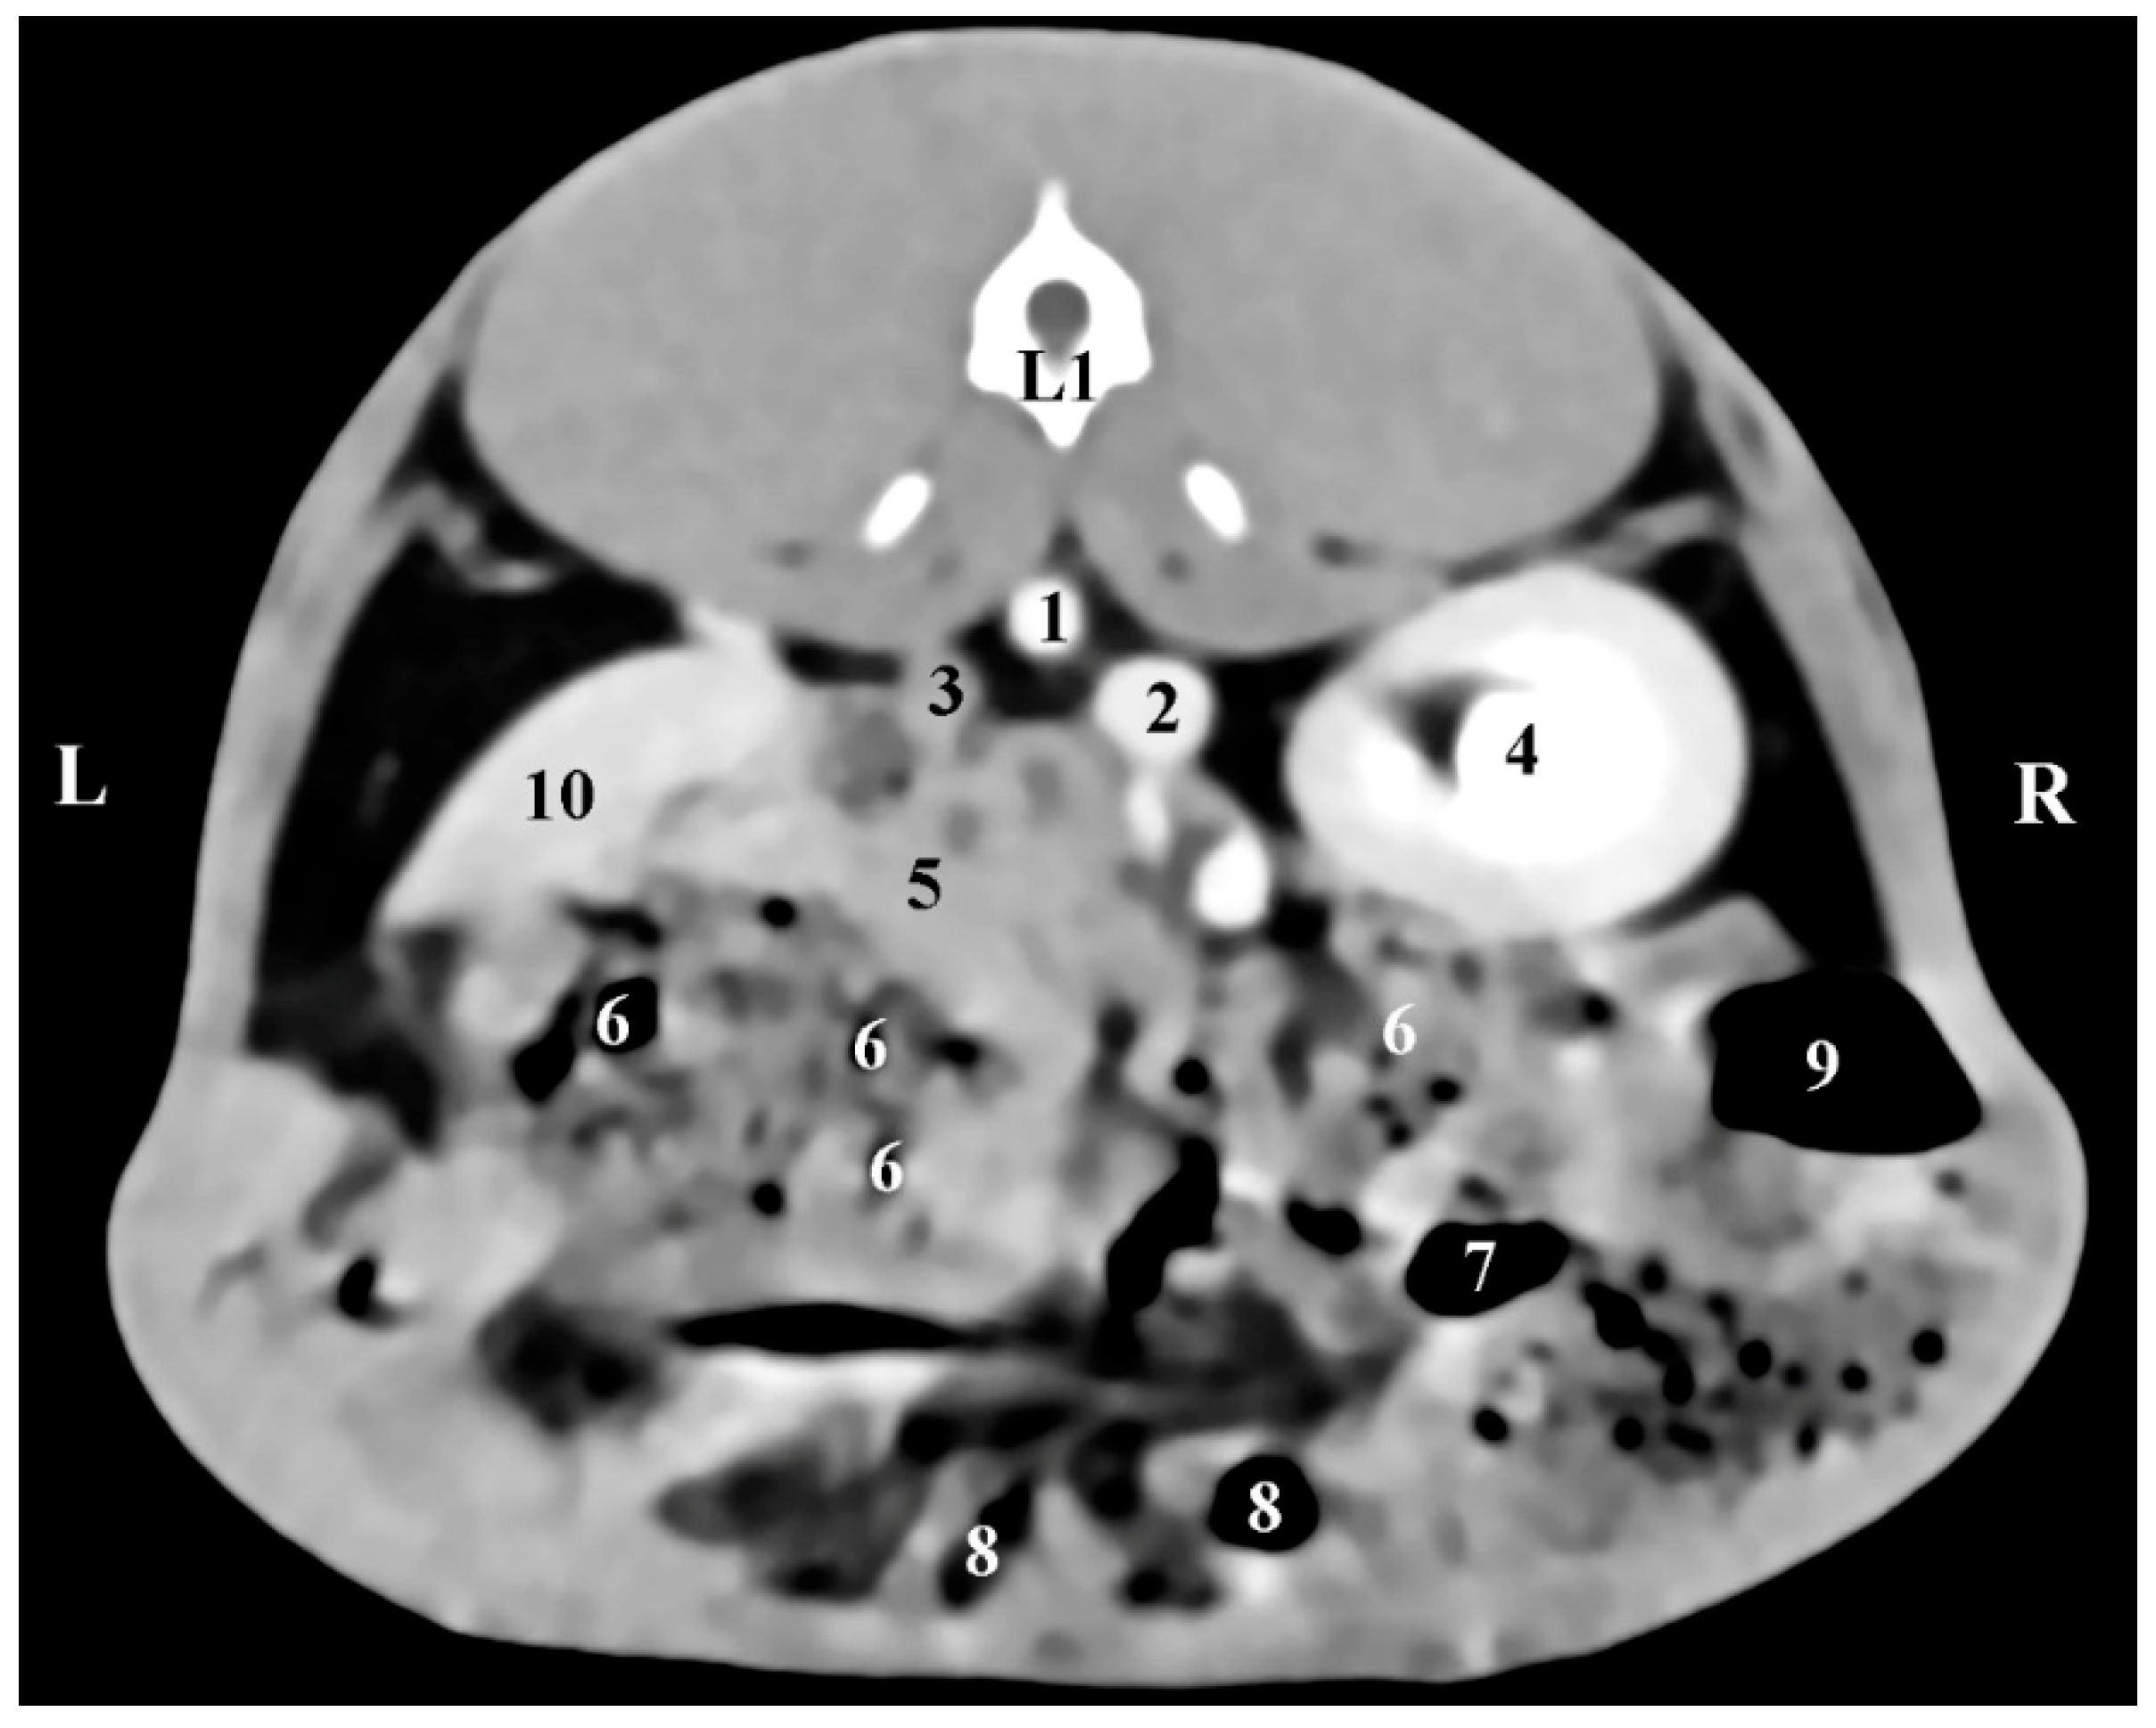

The dorsal (coronal) post-contrast anatomical CT study of regio abdominis through the dorsal plane 30 mm ventrally to the spine showed the elliptical shape of the homogeneous and sharply delineated image of the right adrenal gland. The gl. adrenalis dextra was located in the regio abdominis lateralis dextra of the regio abdominis media. The gland was retroperitoneally located, medially in contact with the v. cava caudalis, and was observed craniomedially to the hyperattenuated borders of the right kidney and caudally to the Proc. caudatus of the caudate liver lobe, with which it was in anatomical contact. The border between them was defined by hypoattenuated contours of the impression of the right adrenal on the proc. caudatus. Dorsally, the gland was in contact with the m. longissimus (Figure 5).

Figure 5. Dorsal (coronal) CT post-contrast anatomical study of the rabbit abdomen (at the plane 30 mm ventral from the vertebral column). CR—cranial; CD—caudal; R—right; L—left. (black star) right adrenal gland; (1) Right kidney; (2) left kidney; (3) right adrenal gland; (4) liver; (5) fundus et corpus ventriculi; (6) v. cava caudalis; (7) aorta abdominalis; (8) longissimus muscle; (9) impression of the right adrenal gland; (*) proc. caudatus.